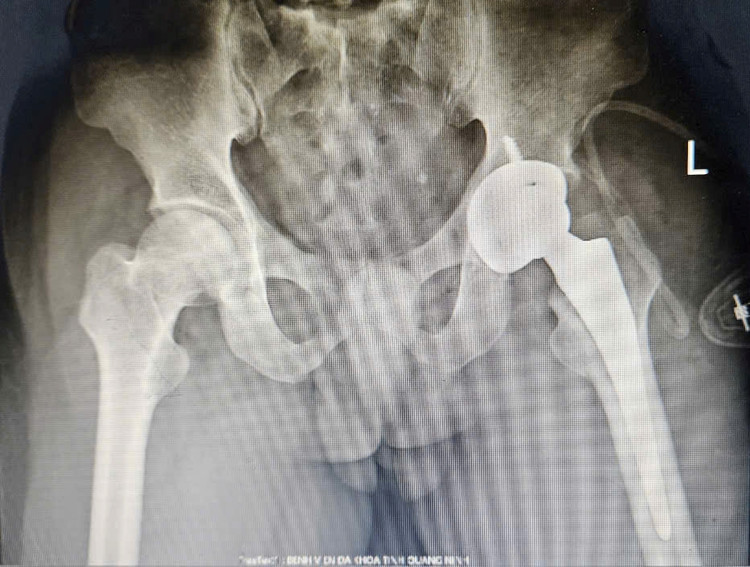

Gần đây, tình trạng đau nhiều khớp háng trái, hạn chế vận động ngày càng tăng nên đến Bệnh viện Đa khoa tỉnh thăm khám. Kết quả chụp X-quang đánh giá, bệnh nhân bị hoại tử chỏm xương đùi giai đoạn 3, cần phẫu thuật thay khớp háng trái toàn phần.

Sau đó, chỏm xương đùi trái bị hoại tử đã được kíp mổ loại bỏ và thay thế bằng khớp nhân tạo. Ca phẫu thuật diễn ra thuận lợi trong 60 phút, bệnh nhân mất ít máu do hạn chế tổn thương cơ và mô quanh khớp. Ngày thứ 2 sau mổ, người bệnh đã đứng dậy và tập đi lại nhẹ nhàng.

| Bệnh nhân tiêu chỏm xương đùi được thay khớp háng trái nhân tạo bằng kỹ thuật SuperPath. - Ảnh BVCC |